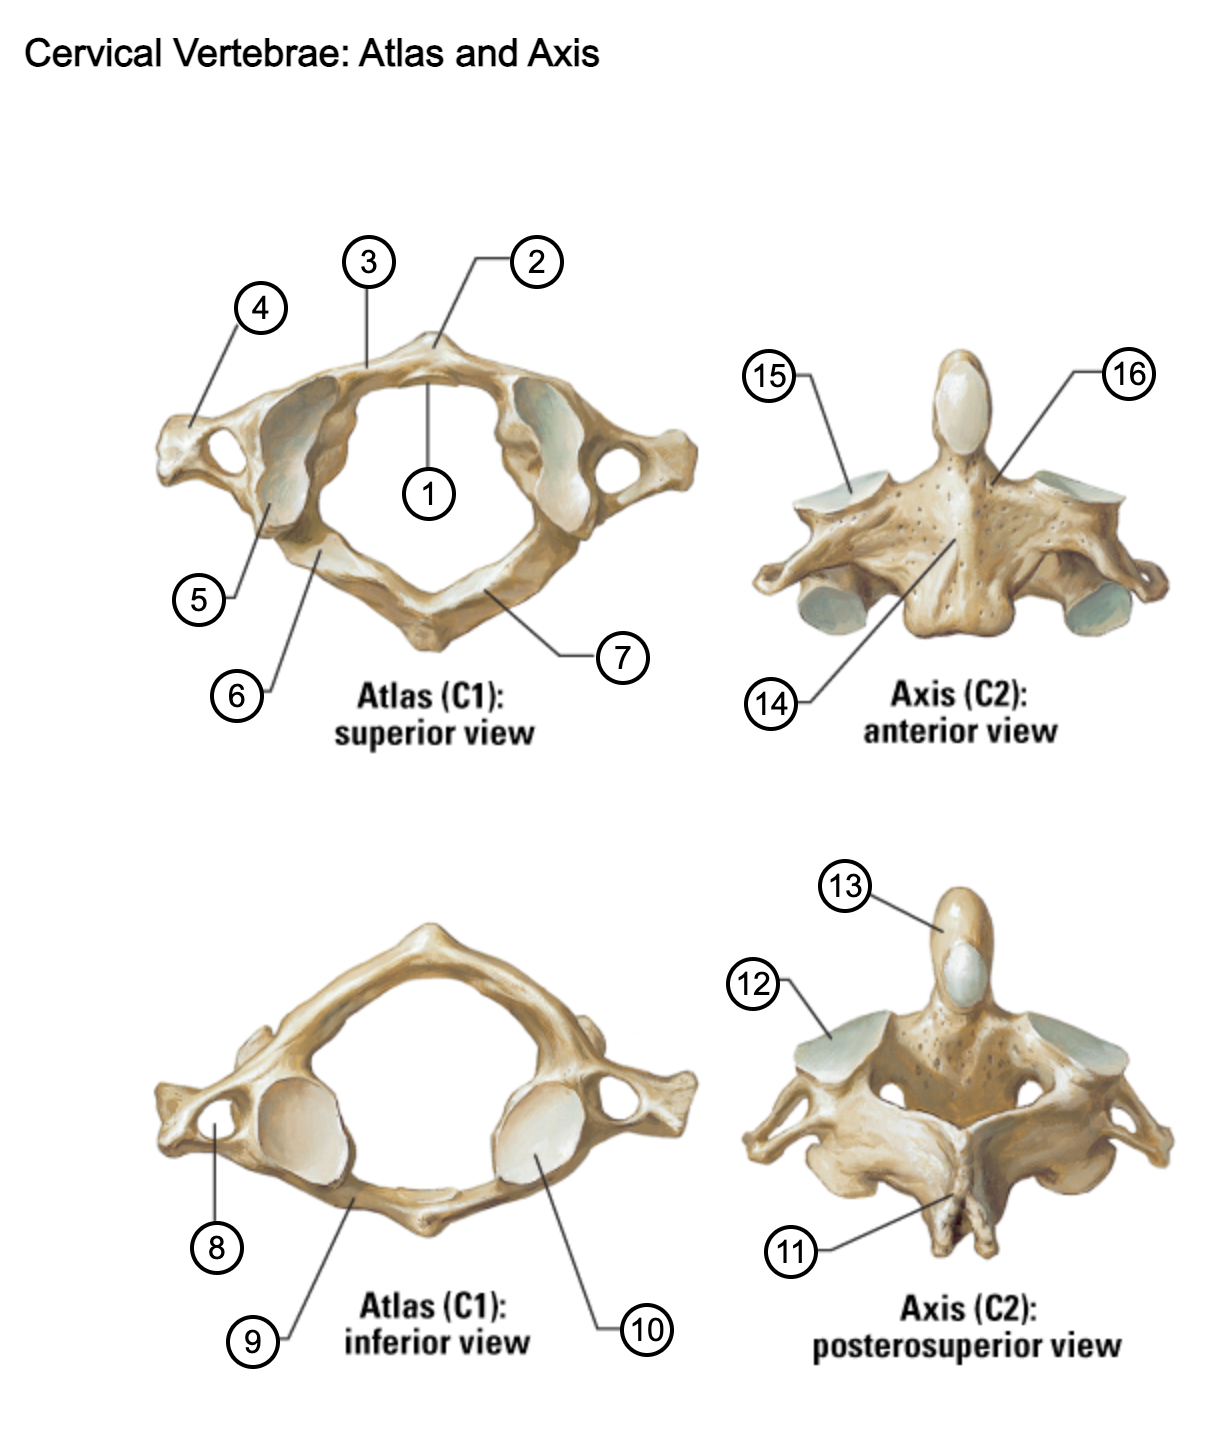

1

facet for dens

2

anterior tubercle

3

anterior arch

4

transverse process

5

superior articular surface of atlas

6

groove for vertebral artery

7

posterior arch

8

transverse foramen

9

anterior arch

10

inferior articular surface of atlas

11

spinous process

12

superior articular facet

13

dens of axis

14

body of axis

15

superior articular facet for atlas

16

pedicle of vertebral arch